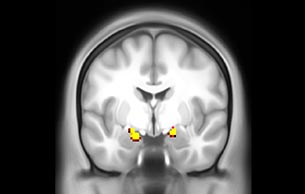

Imaging was performed using Ingenia 3T CX with a 32ch dS Head coil, TR 1.6 sec, TE 35 ms, voxel size 3.1 x 3.1 x 3.1 mm, 46 slices and Multiband SENSE factor 2. Image provided by Dr. Gispert

Default mode network as discovered by resting state fMRI in one participant of the ALFA cohort [7]. rs-fMRI allows us to find networks of brain regions with highly correlated activity and sustaining distinct brain functions. The default mode network (in warm color scale) is active when the brain is focused on introspective thinking and has been shown to be altered in Alzheimer’s. Interestingly, brain areas of this network are known to show abnormal levels of one of the pathological hallmarks of Alzheimer’s (b-amyloid deposition) in preclinical stages. We want to better understand the alterations of these brain networks in preclinical stages of Alzheimer's and explore their potential use as biomarkers.